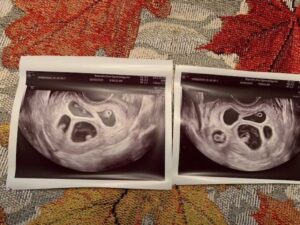

I went in the following week for an early ultrasound because I was at high risk for ectopic pregnancy because of my left side being blocked. We had a resident doctor doing the ultrasound. She said everything looked good, but something seemed off. She said it looked like I had ovulated from the left side. ‘That’s impossible,’ I thought to myself. When my fertility specialist came into the room, the first thing she said when she looked at the screen was, ‘I see twins!’

I was so excited and before I could even tell Jake, ‘I told you so,’ the doctor’s face went pale and she said, ‘I think there are five.’ My left side was indeed not blocked. Excited turned to shock and disbelief. Being less than 6 weeks along, we weren’t able to see heartbeats yet, and she told us most likely they wouldn’t all survive but to come back in 2 weeks.

During those 2 weeks, I could hardly get out of bed. I was absolutely terrified, I didn’t understand why God would do this to me. It was so dangerous! At 8 weeks, we went in and sure enough, we saw five healthy babies! I was actually pregnant with QUINTUPLETS! I somehow lucked out and had a wonderful pregnancy, almost no morning sickness! My only complaints were sciatic nerve pain and migraines. At 16 weeks along, we found out we were expecting three girls and two boys! That’s when I finally started getting excited.